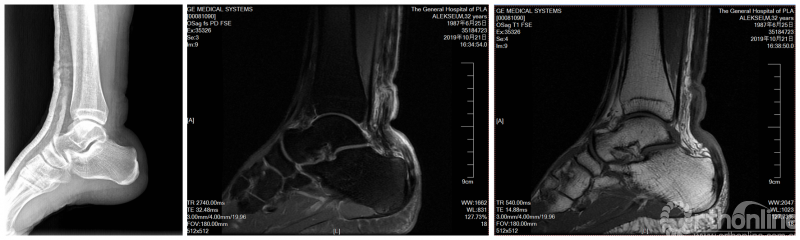

俄方受伤运动员影像学资料:

当日,经核磁共振检查提示右跟腱断裂,经过会诊,决定进行手术治疗。本次手术由第七届世界军人运动会首席医疗官团队秘书长魏世隽亲自主刀。